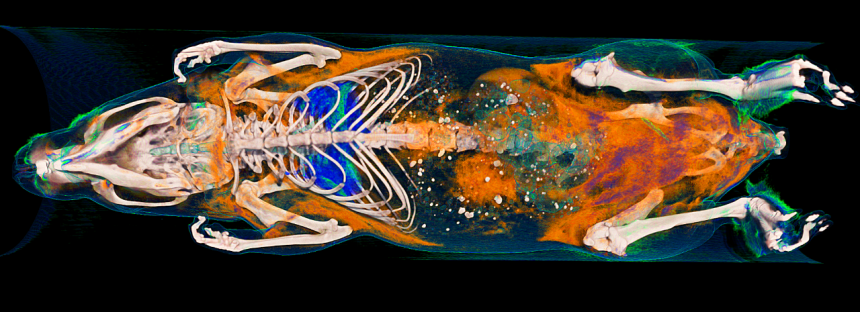

Body composition

Calculating and visualizing body composition of the mouse or rat is easily accomplished in just a few steps. No additional contrast agent is needed to analyze body fat as it is one of the naturally occurring x-ray densities in the body, the others being lean tissue, lung tissue and bone. With the SKYSCAN 1278 body tissue composition analysis can be highly automated and high-throughput, suitable for genetic screening.

- Fastest scan of only 7.2 seconds and streamlined operation makes high throughput of mice or rats easy to obtain. Optimized filters and voltages ensure the least possible radiation dose.

- Full in-house software solution for tissue segmentation and 3D analysis, 3D registration of sequential scans to map progression with growth and time.